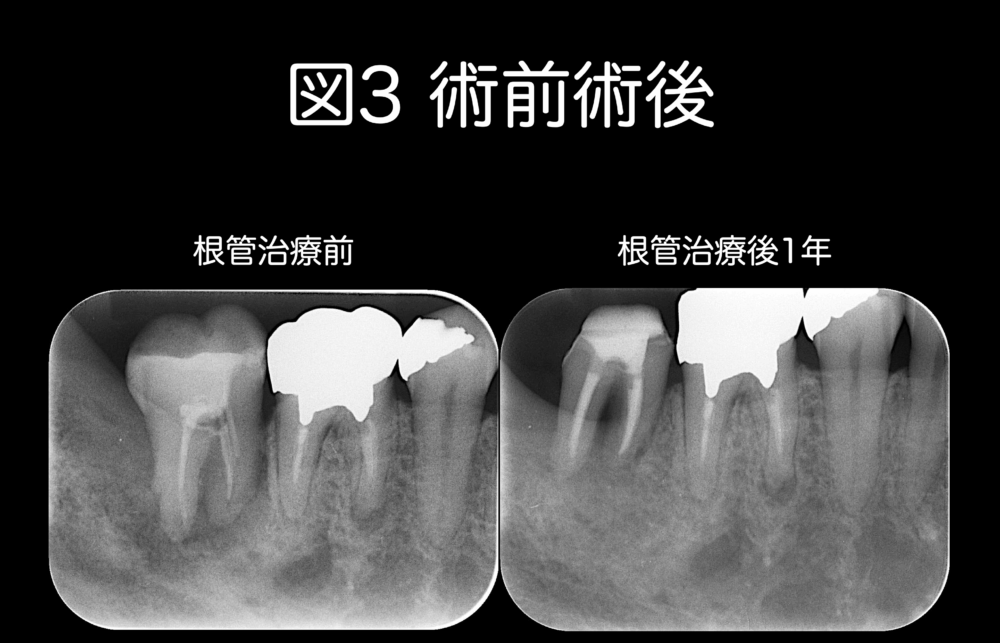

図2のケースの術前術後を図3に示します。

患者さんの主訴は、かむと痛いでした。

初診時、歯が揺れていて歯周病も併発していました。

レントゲンでは髄角の取り残しは不明です。

このケースを治療するかどうかは、議論されるところではありますが、患者さんは保存を希望され、根管治療を行いました。

治療した結果、歯の揺れは治り、かむと痛みもなく、歯周病も改善しています。

症状が改善した原因の1つに、髄角を除去したことが含まれるケースでした。